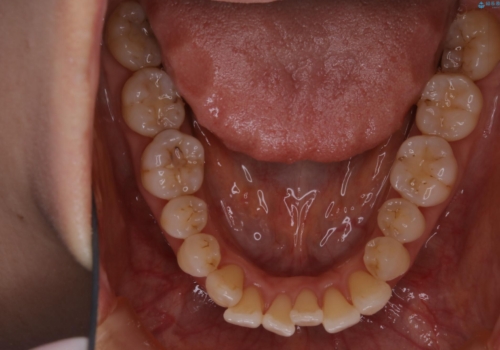

インビザラインによる非抜歯矯正を行いました。

IPRと呼ばれる、歯と歯の間を削る処置を行い、

がたつきを改善し歯を内側に入れることに成功しました。